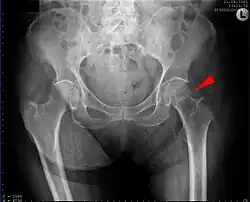

X-ray of a normal hip joint.

Fracture (black arrow, pertrochanteric) versus a skin fold (white arrow).